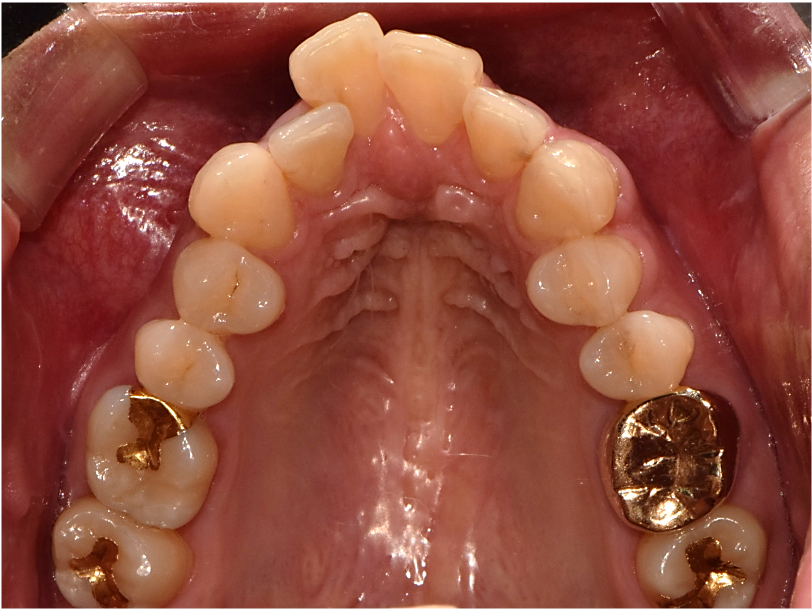

상악 악궁이 좁을 경우에는 하악을 편안하고, 안정적으로 수용하지 못하기 때문에 치아의 배열이 고르지 못하고, 이로 인해 돌출입, 주걱턱과 같은 문제가 생기게 됩니다. 이러한 경우 악궁확장을 통해 미리 증상을 예방하거나 이미 문제가 발생한 경우 시행하여 안정적이고, 바른 치아배열을 만들 수 있습니다. 아래사진은 주걱턱 개선을 위해 양악 수술을 할 줄 알고 큰 근심을 가진 환자를 상악궁 확장을 통한 비수술-비발치 교정으로 치료한 증례입니다.

좁은 악궁을 가진 케이스